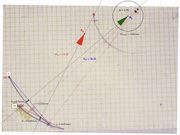

| 10:23, 21 July 2024 | Rototraslazione Y.jpg (file) |  |

137 KB | Gianni | 1 | |